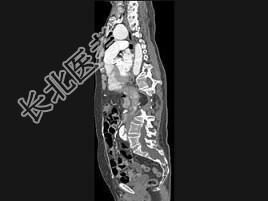

- 单项选择题男,24岁, 四肢细长,蜘蛛指, 肌张力降低,结合图像, 最可能的诊断是 ( )

C、马方综合征